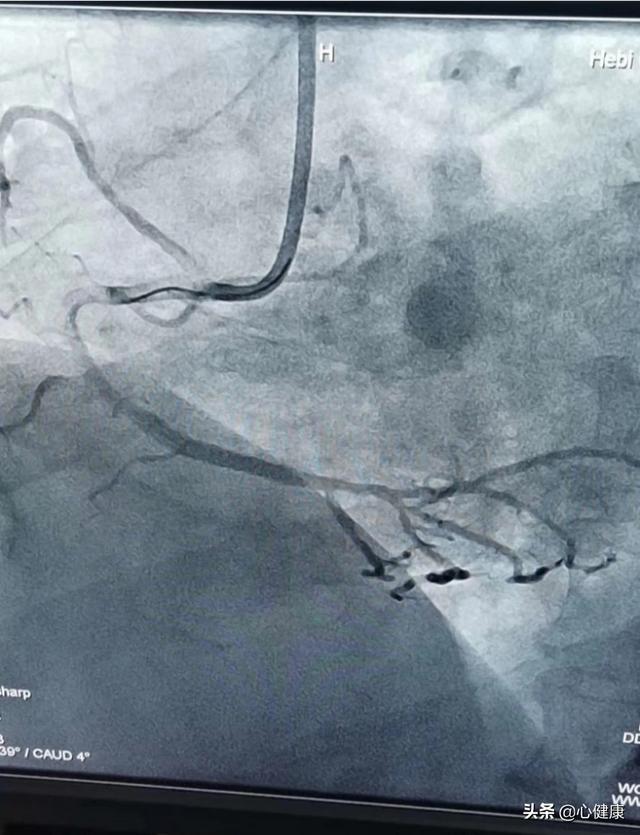

まず、冠動脈の狭窄が70%を超えると、狭窄がより深刻になっていることを示す。一般的に、冠動脈の50%以上の狭窄は冠動脈への血液供給が不十分である可能性があり、冠動脈性心疾患はすでに診断できる。そして冠動脈の70%以上の狭窄は間違いなくより深刻な狭窄と考えられ、労作性狭心症のエピソードを引き起こす可能性がある。しかし、70%の狭窄であっても、激しい運動による酸素消費量の激増でない限り、一般的な日常生活における血液供給はまかなえるので、あまり心配する必要はない。しかし、冠動脈疾患のある患者さんには、心室拍出量をコントロールし、心筋の酸素消費量を減らし、狭心症の発生を抑えるために、メトプロロールを服用する必要がある。

冠動脈狭窄が70%を超えてからステント留置が必要かどうかについては、病態や狭窄部位によって総合的に判断すべきであり、一概には言えない。急性梗塞症例ではステント留置は早ければ早いほどよいが,非ST上昇型急性冠症候群(不安定狭心症または非ST上昇型心筋梗塞)の患者や心血管危険因子が大きい中等度リスク群以上の患者では,ステント留置のタイミングは異なる選択が必要である。安定狭心症の患者では、冠動脈狭窄が70%に達したとしても、ステントを留置する場合としない場合とで予後や症状の改善に統計的な差はない。冠動脈3枝病変、左主幹病変や左主幹分岐部病変、太い冠動脈の分岐部病変、心室壁瘤を合併した冠動脈病変、心室間隔の穿孔、僧帽弁閉鎖不全、その他の心内膜の構造異常がある場合には、冠動脈バイパス移植術の方が適切かもしれない。

最後に、冠動脈ステント留置術を選択するか否かにかかわらず、プラーク安定化のためのスタチン系脂質低下薬や血小板凝集抑制のためのアスピリンなどの抗血小板薬のような標準化された薬物療法の代わりにはならない。

心血管系の血管をどの程度ステント留置する必要があるかは、まず心血管自体の狭窄の程度という2つの点によって決まる。

次に、狭窄が患者に何らかの症状を引き起こしているかどうかである。心臓の血管自体の狭窄の程度が通常70%以上で、虚血に関連した胸痛などの症状があれば、ステント留置を考慮する。

一般的に血管が狭くなる最も一般的な要因は冠動脈の動脈硬化であり、これが対応する症状を引き起こし、将来的には心筋梗塞を引き起こす可能性もある。

したがって、冠動脈狭窄の程度を評価するための冠動脈造影は、ステント留置が必要かどうかを決定する上で不可欠である。